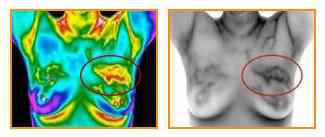

As we know early detection and alternative prevention save a life! So, why not we opt the best Thermography Screening that helps the Cancer patient to detect the Cancer at the initial stage, and reduce the death rate. So, wait no more and get the best Infrared Thermography Services in Sarasota, FL today! https://www.flowwell.org/thermography/ [more]

To detect the Breast Cancer at the intial level, select the reliable Breast Thermography Center today! https://flowwellusa.wordpress.com/2018/10/12/find-the-reliable-center-for-breast-cancer-check-up/

Infrared Breast Thermography - A Good Option to Monitor Breast Cancer at Early Stage http://flowwell.blogspot.com/2018/08/do-not-wait-for-tragedy-get-medical.html

The first step in fighting a disease starts with early detection. Then fix it and prevent further. With the help of Thermography Cancer Screening you can get the exact information about the direction of your disease and diagnosis. So, what are you thinking? Go ahead and initiate your search for Infrared Thermography Services in Sarasota, FL right away! https://www.flowwell.org/thermography/